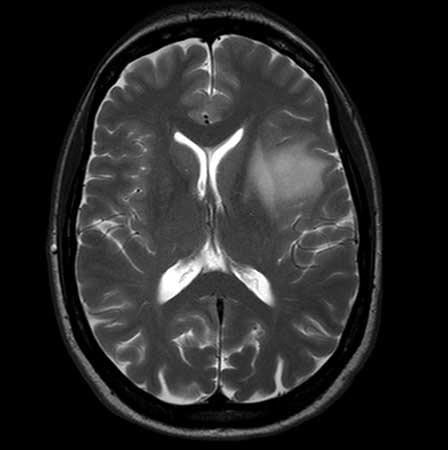

Advanced MRI Center

Advanced MRI Center

The Advanced MRI Center CORE facility provides the latest magnetic resonance imaging and spectroscopy capabilities to scientists, clinicians, government and industry, along with technical and clinical expertise for collaborative research.

The Center’s specialized techniques clarify functional, physiological and biochemical information from all organs of the body, enabling physicians to make more informed patient-care decisions. Additionally, researchers are better able to understand the mechanisms of such conditions as lung and heart disease, cancer, stroke, epilepsy, multiple sclerosis, lupus, rheumatoid arthritis, osteoarthritis, osteoporosis, back pain and injuries, autism, Alzheimer’s disease, bipolar disease and depression. This facilitates the development of new therapies that can be safely and continuously evaluated throughout patient treatment.

The Advanced MRI Center houses:

- 3T Philips Achieva whole-body scanner complete with a full array of clinical and animal RF coils

- Comprehensive physiologic monitoring system

- Anesthesia infusion pump

- Contrast injector

The Advanced MRI Center is on A-level of the UMass Chan Medical School.

Manojkumar Saranathan, PhD, Co-Director

Mohammed Salman Shazeeb, PhD, Co-Director